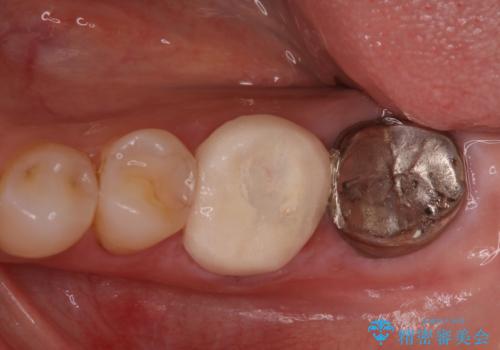

他院で仮歯までしたが、放置していたためセラミック入れたい セラミック治療

- 他院で、仮歯にしたがセラミックの値段が高すぎると思ったため治療相談も含めて来院された患者様です。

仮歯を新調させていただき、再度虫歯治療を行なって、歯の形を作りセラミックを入れさせていただきました。

にて治療させていただきました。色に関しても喜んでいただき満足されていました。